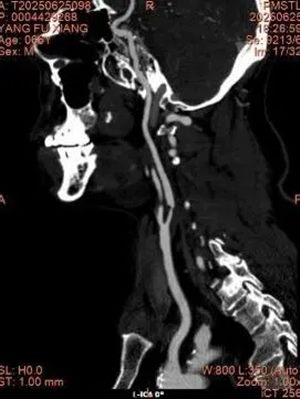

▲ 术前造影

在血管外科崔文军主任、安乾副主任、王浩医师紧密协作和美国芝加哥大学医学中心(University of Chicago Medical Center)Dr. Ross Milner 教授的现场技术指导下,手术团队精准操作,顺利完成了这台具有里程碑意义的TCAR手术。

手术患者为一位老年男性,因体检发现左侧颈动脉狭窄入院。经入院详细检查,确诊颈动脉左侧重度狭窄。